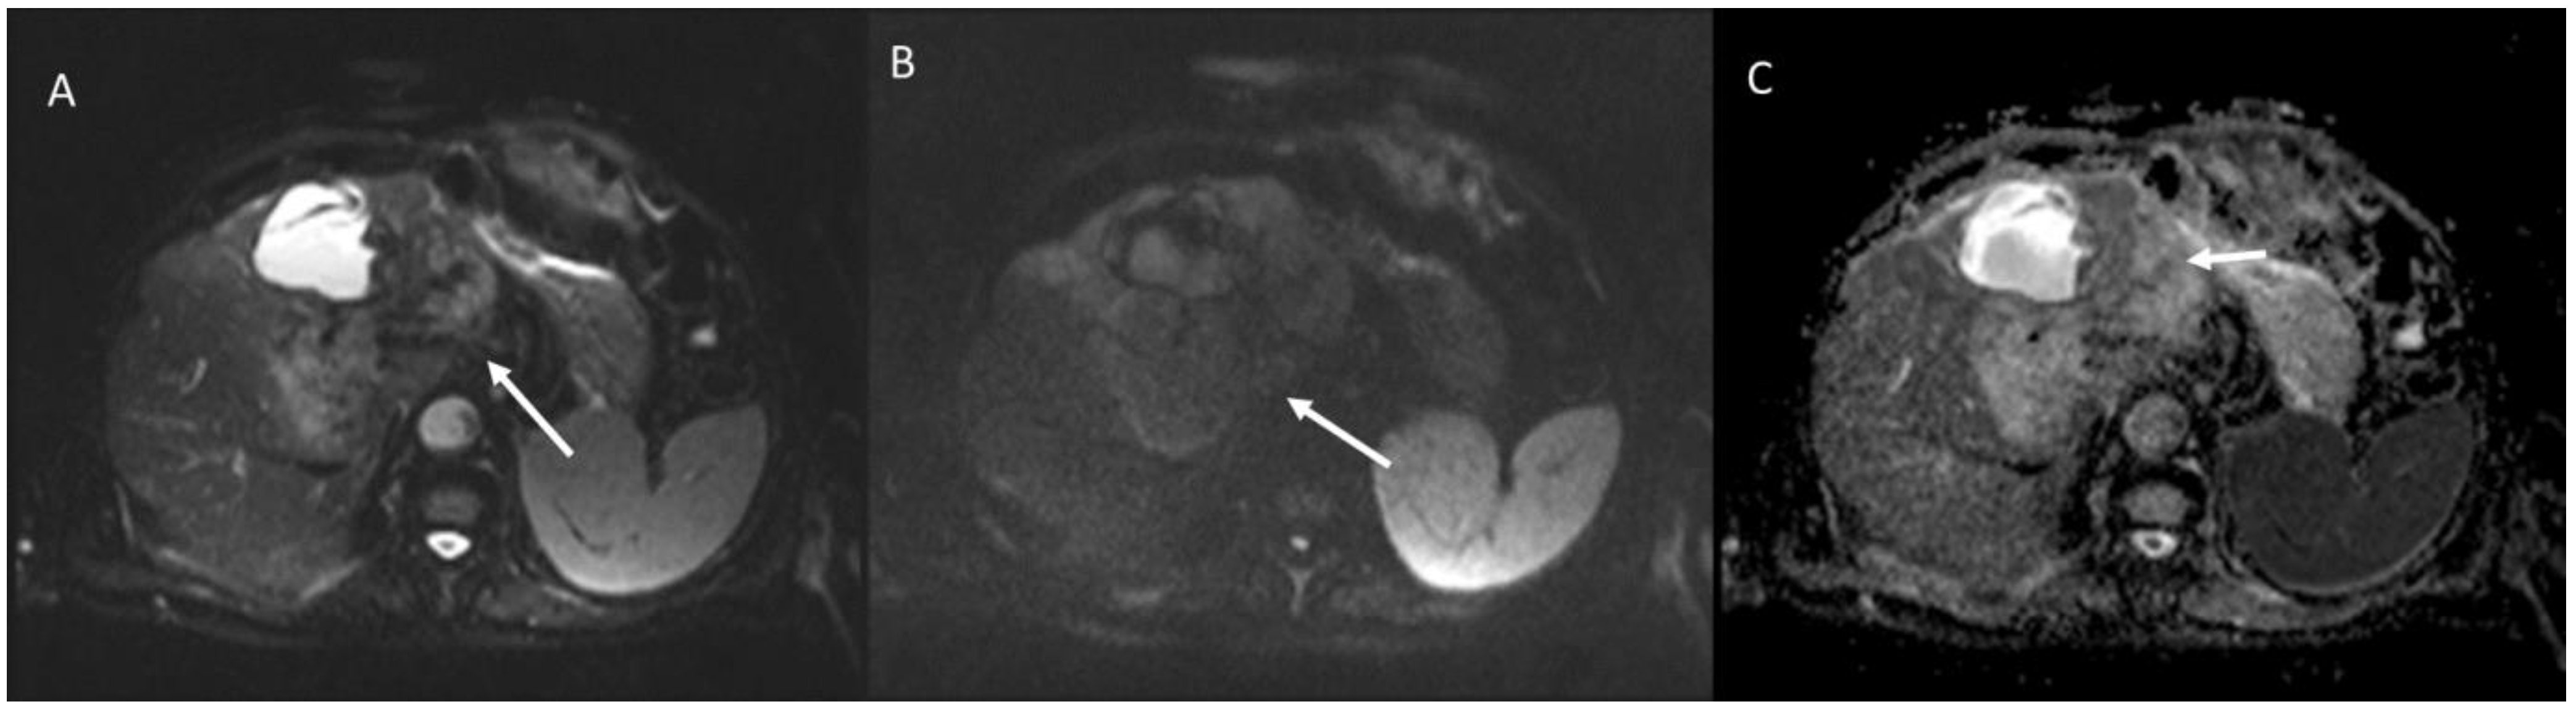

3. Primary Sclerosing Cholangitis

6.5. Diagnostic Management